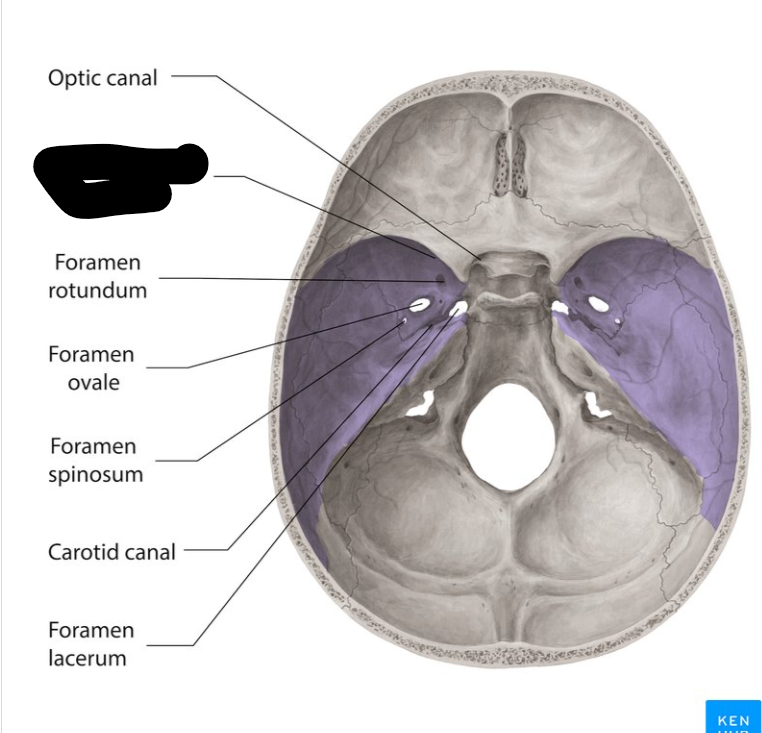

Middle cranial fossa

Foramen rotandum

Foramen ovale

Foramen lacerum

Foramen spinosum

Superior orbital fissure

Optic canal

Carotid canal